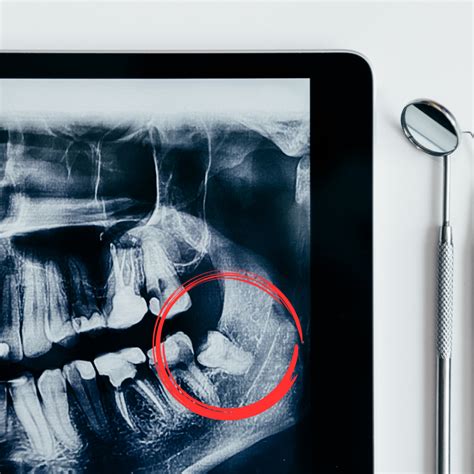

Evaluación Previa

Antes de programar la cirugía, examinaremos tu boca y tomaremos radiografías panorámicas o 3D. Así podemos ver la posición de las muelas del juicio y su relación con el hueso, los senos maxilares (en el caso de superiores) o el nervio dentario inferior (en el caso de inferiores). Con esta información, planificamos la extracción de la forma más segura.

El mayor porcentaje de extracciones se realiza en pacientes jóvenes, y es más recomendable llevarlas a cabo antes de que se cierre el ápice de las raíces, minimizando así problemas y el riesgo de afectar el nervio dentario. En aquellos casos donde las muelas del juicio tienen un alto compromiso con el nervio dentario, es recomendable solicitar un TAC previo a la extracción.